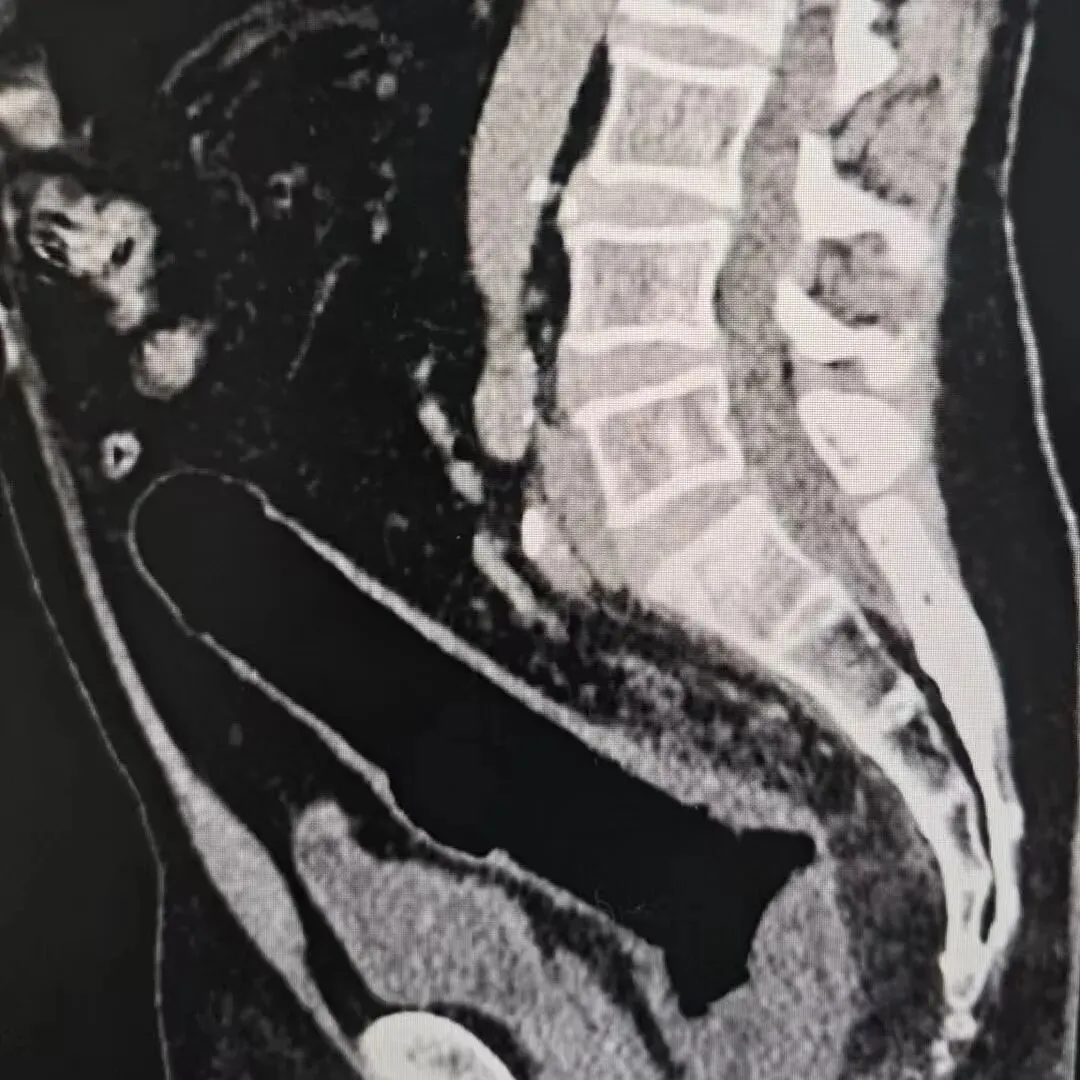

这位中年男性患者就诊时,满脸尴尬地表示,自己不小心坐到假阳具,导致其滑入肛门,能摸到却怎么也取不出来。医生当即建议尽快处理,可患者心存侥幸,觉得 “忍忍就能自己拉出来”,便自行回家了。

异物会在肠道内越陷越深。肠道的自然蠕动和内部负压,会不断将异物往深处吸附,最初可能还停留在直肠口附近,拖久了就可能进入更深的乙状结肠,届时徒手无法取出,内镜操作也会困难重重,最终只能通过手术解决。